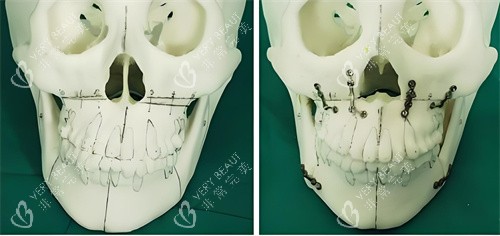

骨骼定型后手术难度翻倍

成年后颌骨像块"老砖头",切割时容易崩裂。陈院长做过对比:18岁前手术,出血量平均80ml;25岁后手术,出血量飙到150ml,术后肿胀时间也延长3-5天。

王芳医生给他的方案是"上颌前徙术":从口腔内切个小口,把上颌骨整体前移3mm。手术用了2小时,出血量不到50ml。术后第5天,小凯就能吃面条;***0天,他已经敢对着镜子咧嘴笑了。